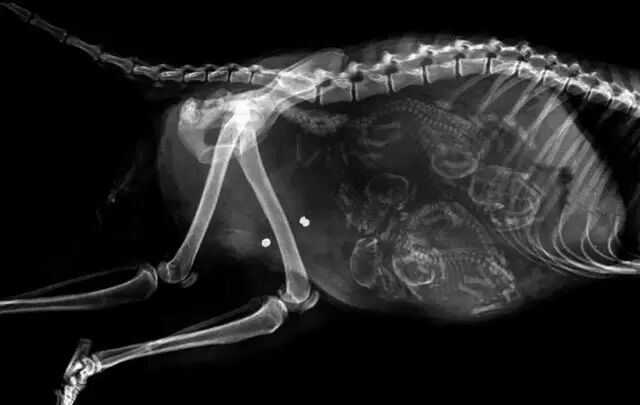

怀孕是一件神圣而又带有神秘色彩的事,她预示着新生命的来临。在动物世界,怀孕是怎样的一种奇迹,以下 14 种动物在怀孕期间的 X 线图片,我们可以通过全新的影像视角探查一番。

• 南美栗鼠